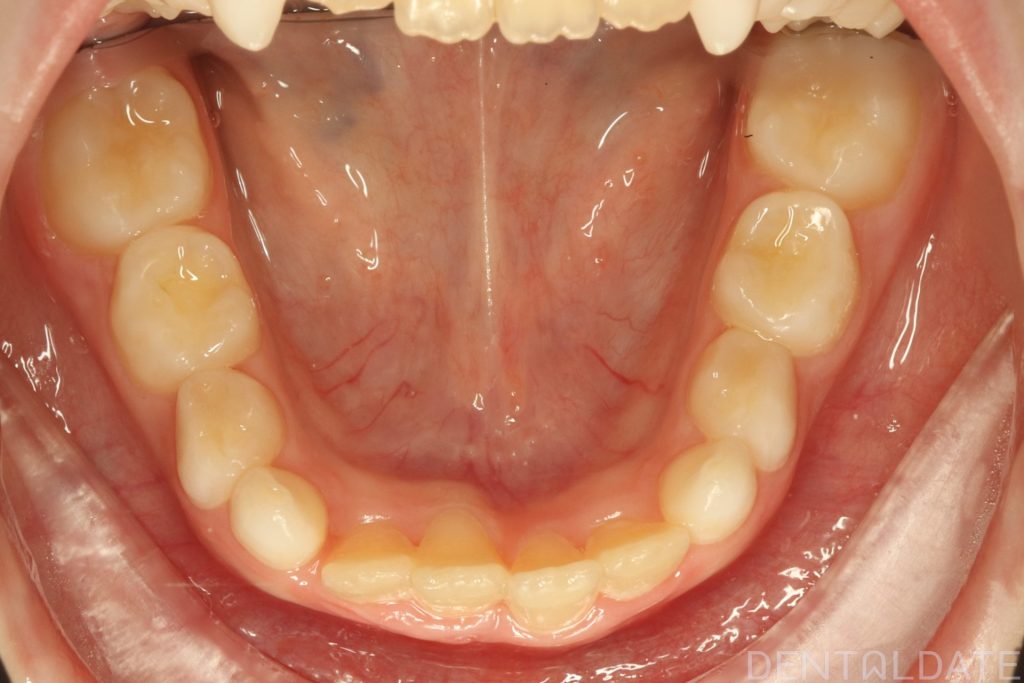

The patient had been undergoing orthodontic treatment at another clinic for 1.5 years with no significant progress.

With a new treatment plan in place -the anterior bite was normalized within just one week.

We are now focused on final adjustments to tooth alignment and occlusal height.